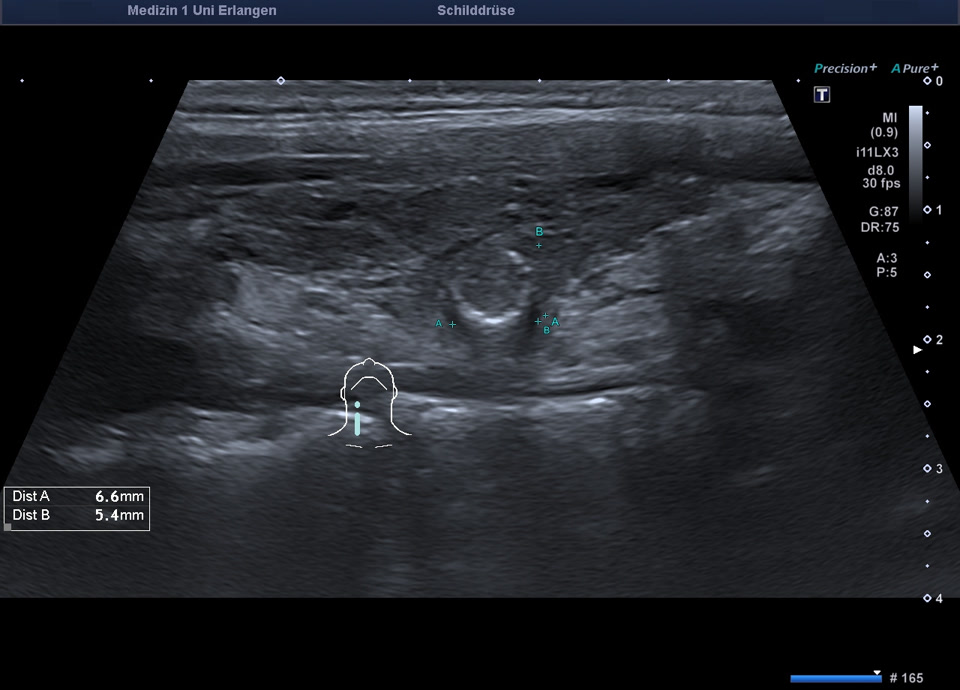

Zystisch regressiver Knoten